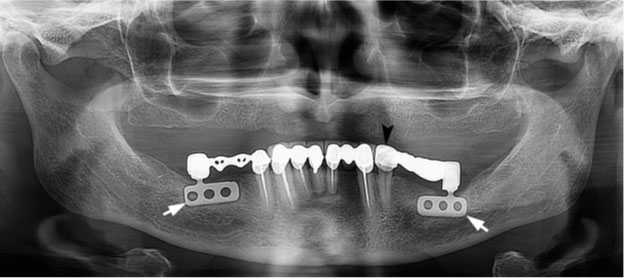

מחלקת התהליכים עמדה ביעד שהוצב לה של אריזת 80,000 שתלים בחודש ביולי, ההישג צוין בארוחת בוקר משותפת ומפנקת.